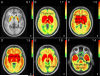

Visualization of target regions for BPND analysis. Target ROIs (A-E) for one representative individual are overlaid on an MRI in axial and coronal views. The cerebellar reference region is depicted in F. To control for partial volume effects, ROIs were eroded when possible. Light blue coloring indicates original, uneroded regions as defined by FreeSurfer or manual tracing. Dark blue coloring indicates eroded regions. BPND's were obtained from eroded areas in all ROIs except for nucleus accumbens, hypothalamus, midbrain, and cortical regions. Sup Temp Sulcus, banks of superior temporal sulcus. rAnt Cing Cortex, rostral anterior cingulate cortex. Trans Temp Gyrus, transverse temporal gyrus. mOrbitofrontal Cortex, medial orbitofrontal cortex.